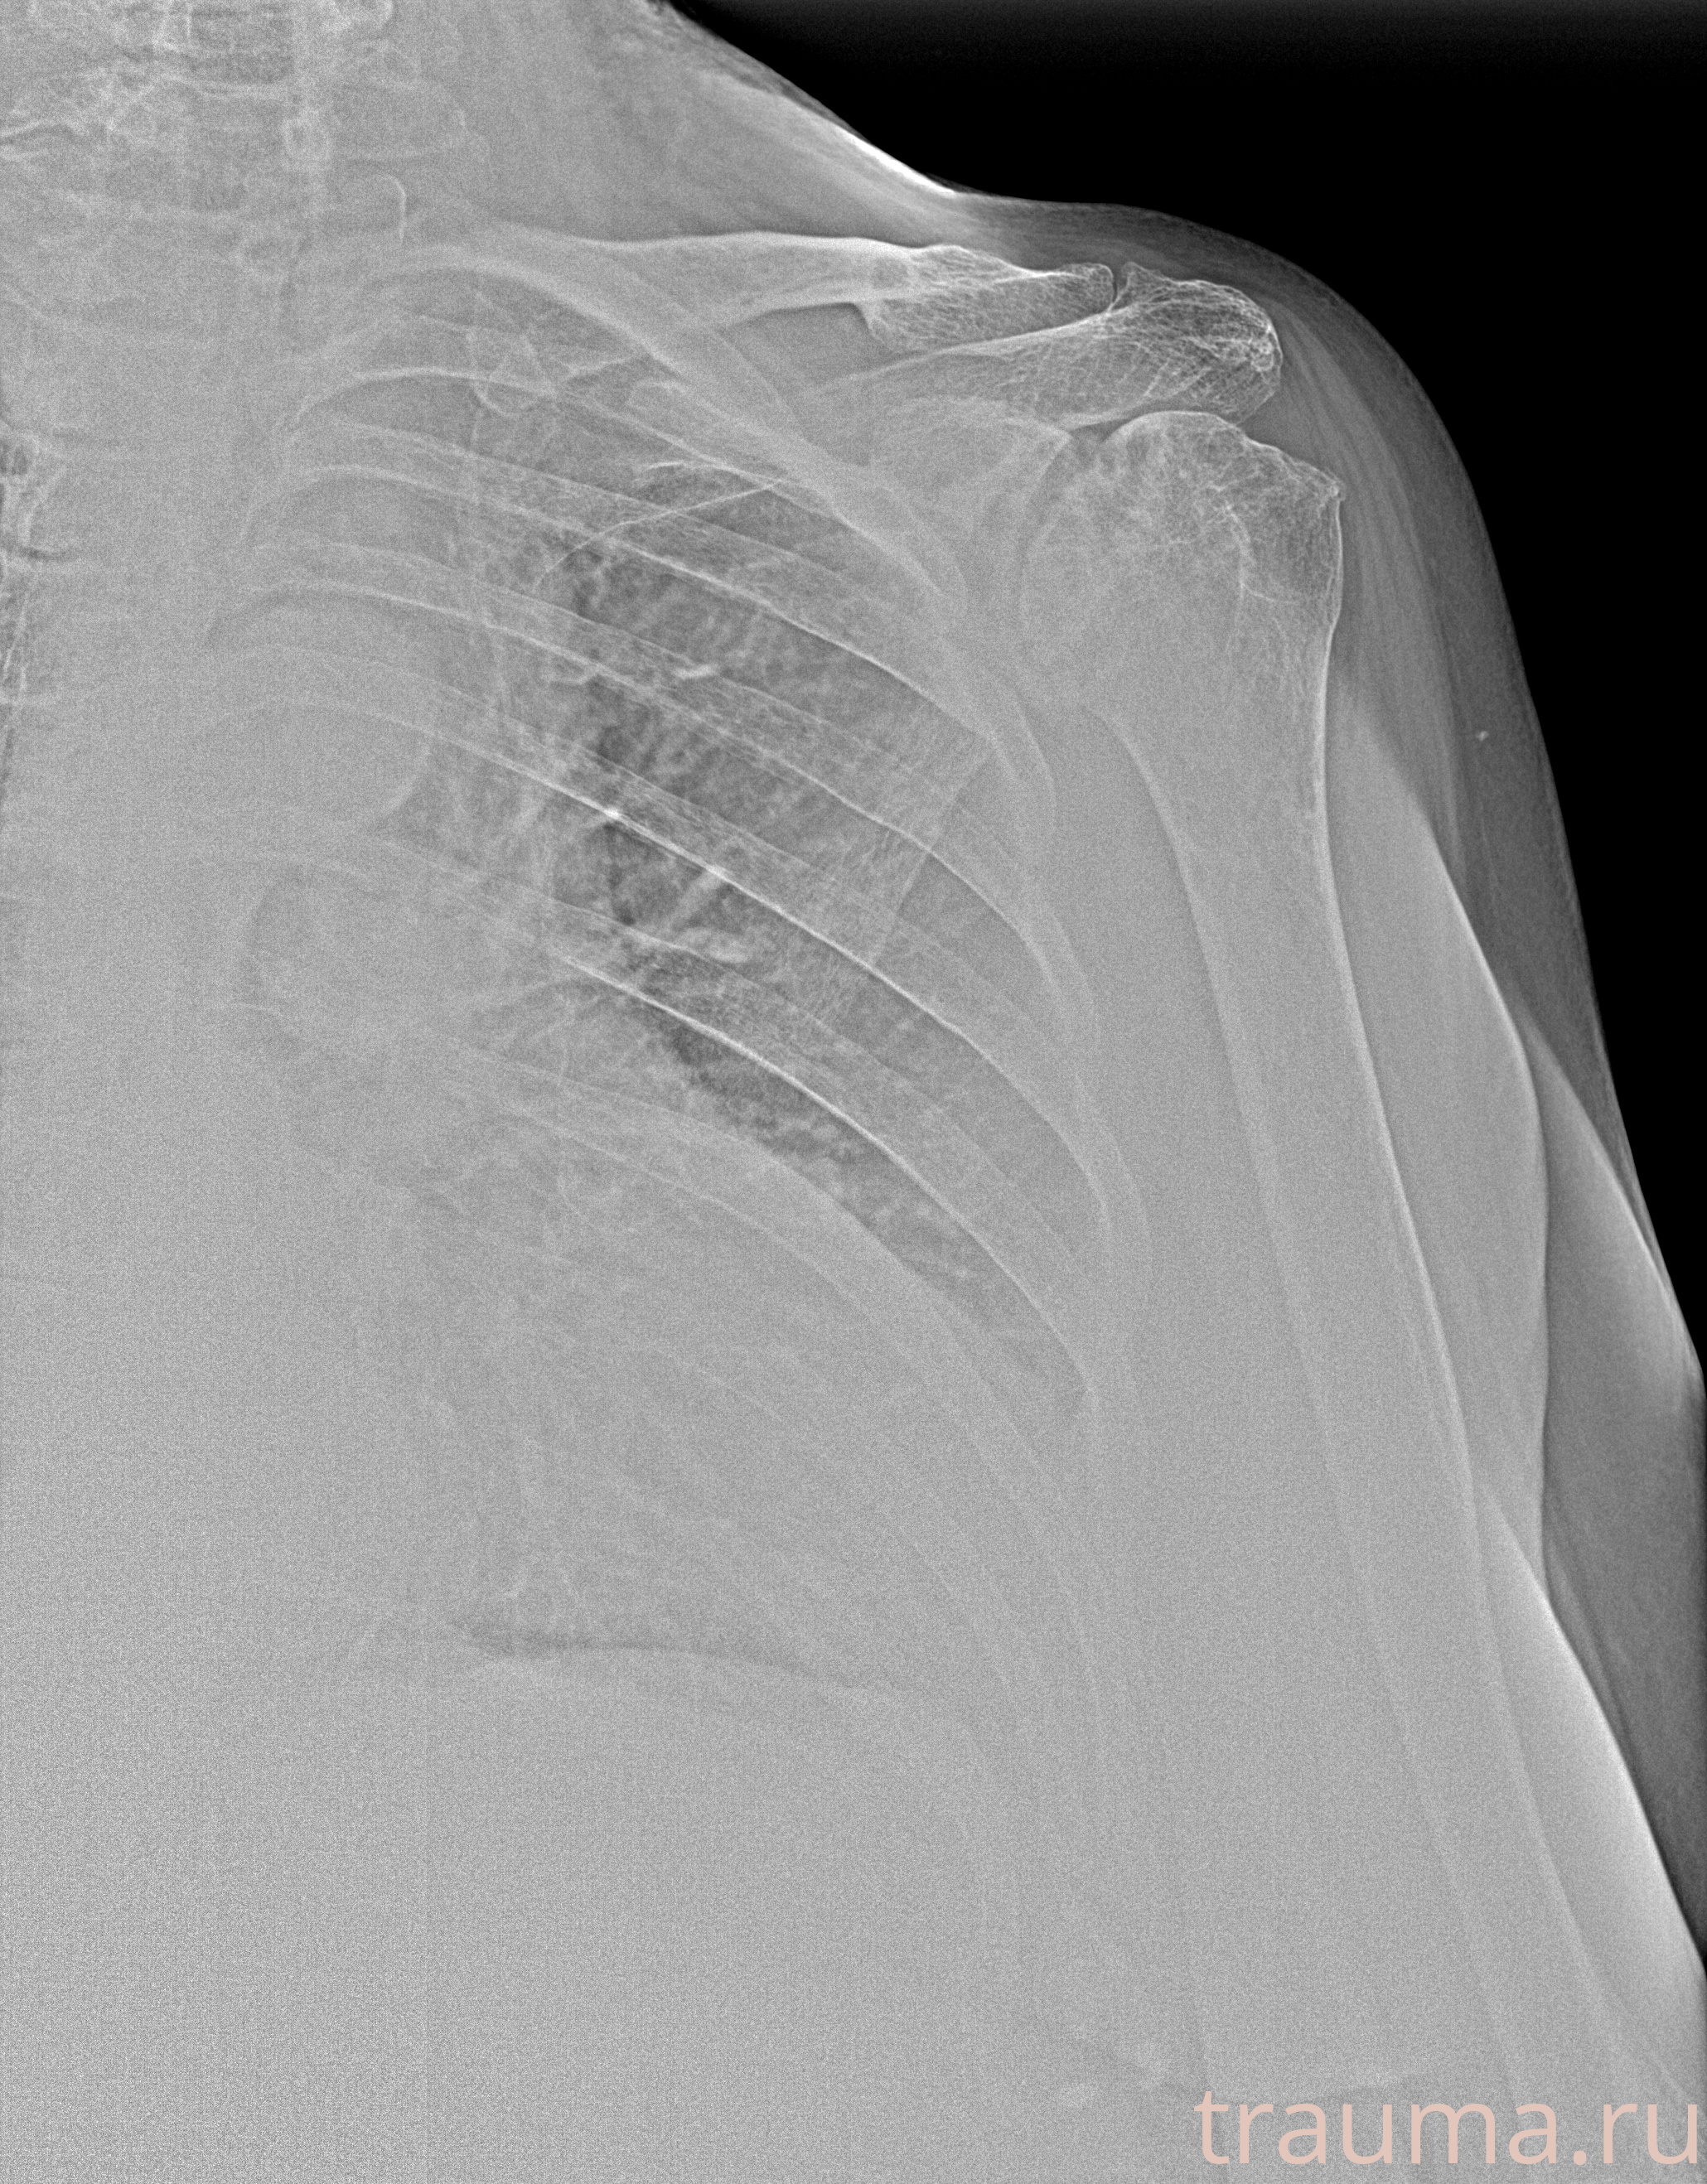

Рентгенограммы

Рентген на дому: по вашему адресу приезжает врач-рентгенолог, травматолог-ортопед с мобильным рентгеновским аппаратом, проводит диагностику травмы или заболевания, делает необходимые рентгенограммы, дает рекомендации по дальнейшему лечению. Получить качественные снимки в домашних условиях возможно благодаря уникальной методике, разработанной МосРентген Центром для института  Склифосовского